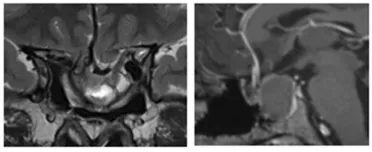

8年逃不過復(fù)發(fā)“魔咒”,突發(fā)中風(fēng)、繼發(fā)空碟鞍綜合征

8年后,小葵出現(xiàn)漸進性視力喪失、上瞼下垂,且突發(fā)腦出血住院,檢查發(fā)現(xiàn)腫瘤復(fù)發(fā),再次進行了手術(shù)。然而這次手術(shù)還是出現(xiàn)殘留。4個月后,患者因視力持續(xù)受損而轉(zhuǎn)至神經(jīng)外科。MRI顯示腫瘤殘余,繼發(fā)性空蝶鞍綜合征伴有鞍區(qū)前交通動脈復(fù)合體的下移位(圖2)。繼發(fā)性空蝶鞍綜合征伴是因鞍隔缺損或垂體萎縮,蛛網(wǎng)膜下腔在腦脊液壓力沖擊下突入鞍內(nèi),致蝶鞍擴大,垂體受壓而產(chǎn)生的一系列臨床表現(xiàn),如蝶鞍擴大,視力減退、視野缺損等表現(xiàn)。

侵襲性垂體瘤實例交流——影像顯示一開始腫瘤切除8年后復(fù)發(fā),并伴有腦出血和鞍底下陷

圖:影像顯示一開始腫瘤切除8年后復(fù)發(fā),并伴有腦出血和鞍底下陷

侵襲性垂體瘤實例交流——術(shù)前MRI顯示二次手術(shù)后腫瘤殘余、患者出現(xiàn)繼發(fā)性空蝶鞍綜合征的影像學(xué)特征

圖2:術(shù)前MRI顯示二次手術(shù)后腫瘤殘余、患者出現(xiàn)繼發(fā)性空蝶鞍綜合征的影像學(xué)特征